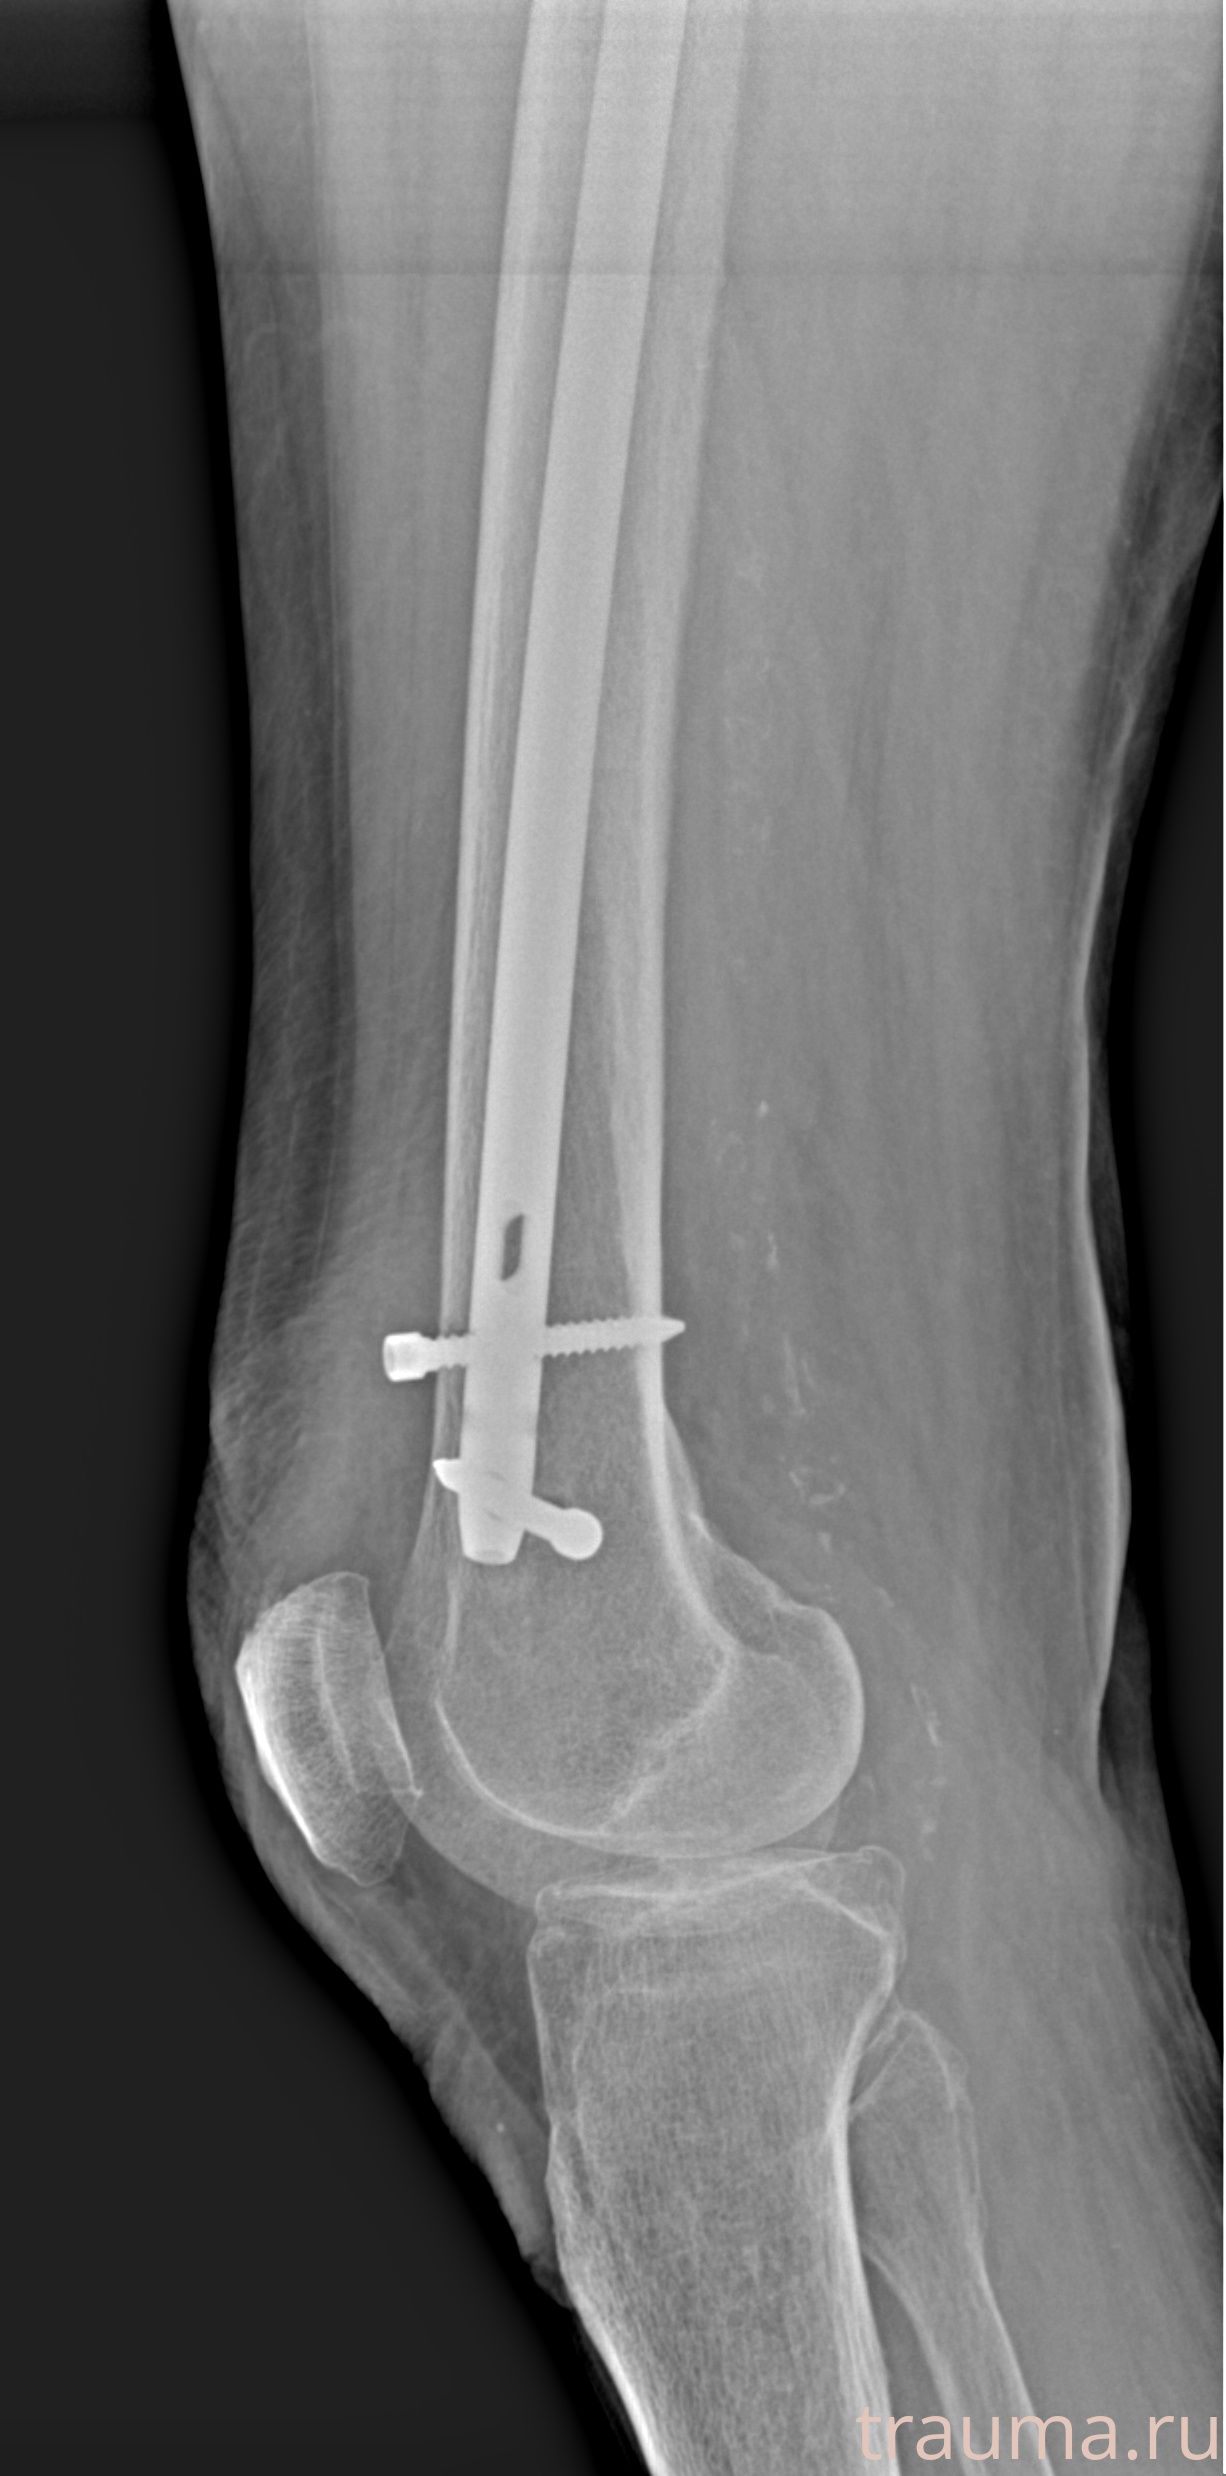

Рентгенограммы

Рентген на дому: по вашему адресу приезжает врач-рентгенолог, травматолог-ортопед с мобильным рентгеновским аппаратом, проводит диагностику травмы или заболевания, делает необходимые рентгенограммы, дает рекомендации по дальнейшему лечению. Получить качественные снимки в домашних условиях возможно благодаря уникальной методике, разработанной МосРентген Центром для института  Склифосовского